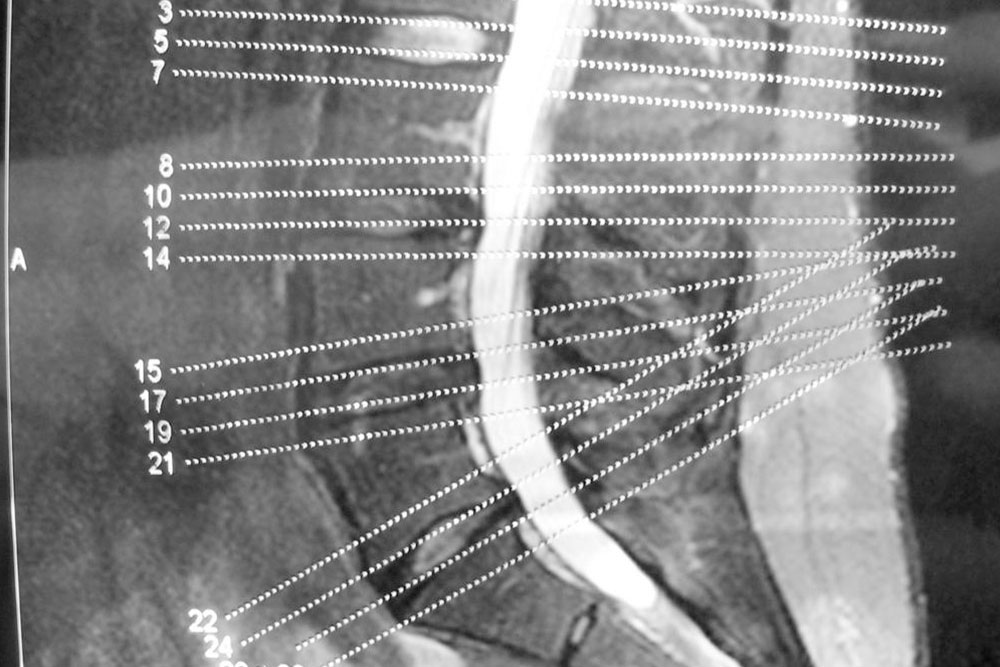

Degenerative disc disease occurs when spinal discs lose elasticity and dry out, losing their shock-absorbing ability. This can cause pain, disc flattening, or tears that may lead to herniation. On the other hand, degenerative joint disease, also called osteoarthritis, affects facet joints. The breakdown of cartilage causes bones to rub, leading to inflammation and pain. Both conditions worsen if untreated but affect different parts of the spine and body.